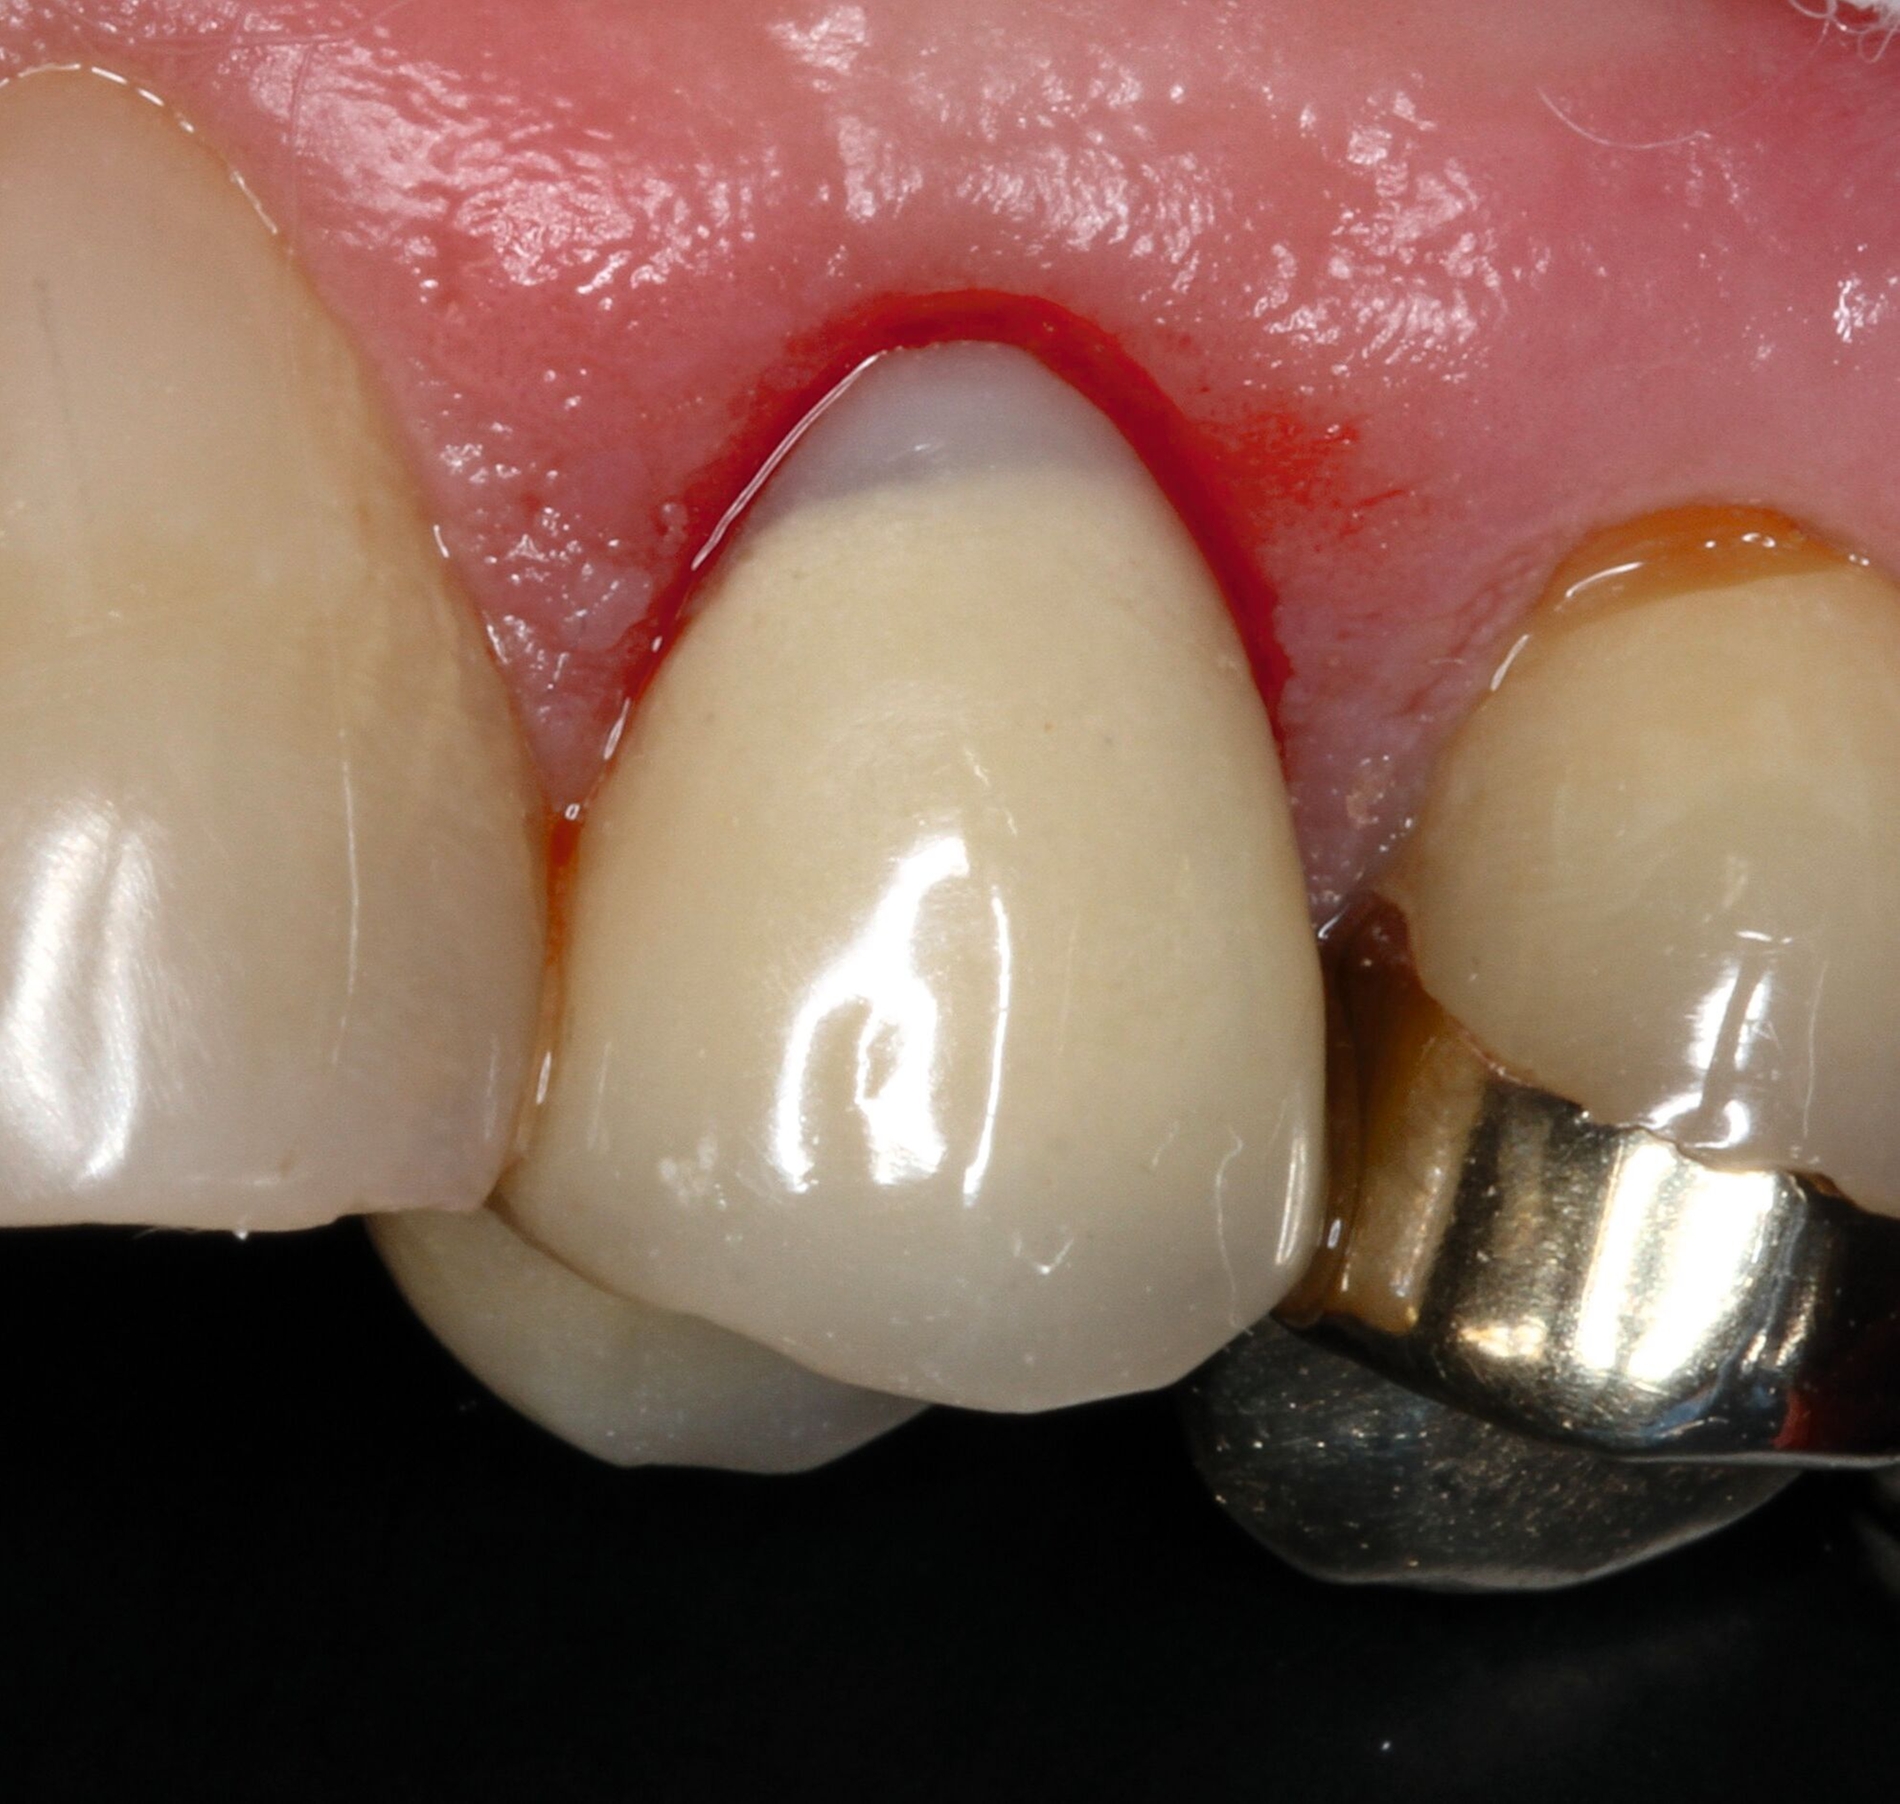

Die keilförmigen Defekte an den Zähnen 14 und 24 empfand der Patient bei Kontakt mit der Zunge als mechanische Irritationsstelle, weshalb eine Kompositreparatur zur Schonung der sonst intakten prothetischen Versorgung und der Zahnhartsubstanz eine sinnvolle und minimalinvasive Option darstellte [Jain et al., 2022]. Dabei wurden Retraktionsfäden zur Defektdarstellung eingebracht, die Dentinoberflächen mit einem Rosenbohrer mechanisch angeraut, die metallkeramischen Kronenränder mit CoJet-Sand silikatisiert, mit einem Silan silanisiert und die gesamte Restaurationsfläche mit einem 10-MDP-haltigen Universaladhäsiv vorbehandelt, um eine suffiziente Haftung zu generieren (Abbildungen 9 und 10) [Lührs, 2015; Stangel et al., 1987; Loguercio et al., 2015; Lührs et al., 2020; Ozcan und Niedermeier, 2002; Hickel et al., 2013]. Aufgrund der stark unterschiedlichen Transluzenz von Kronenmaterial und Komposit war es nicht möglich, eine unsichtbare Reparatur zu erzielen.